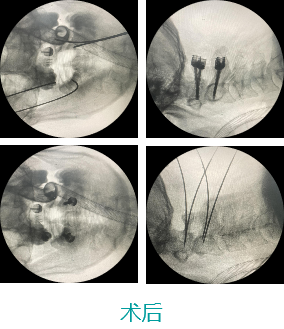

天玑II脊柱手术—颈椎手术

天玑II 辅助颈椎椎弓根螺钉内牢靠术

基本情形:患者男,,,,,49岁,,,,,枢椎骨折

病例泉源:北京积水潭医院